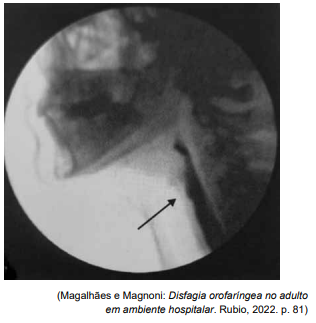

A Videofluoroscopia da Deglutição (VFD) possibilita

a avaliação completa e dinâmica de todas as fases da

deglutição, bem como apresenta grande sensibilidade

e especificidade na detecção de aspiração. Observe a

figura a seguir.

Assinale a alternativa que apresenta uma descrição compatível com o exame apresentado.

Assinale a alternativa que apresenta uma descrição compatível com o exame apresentado.